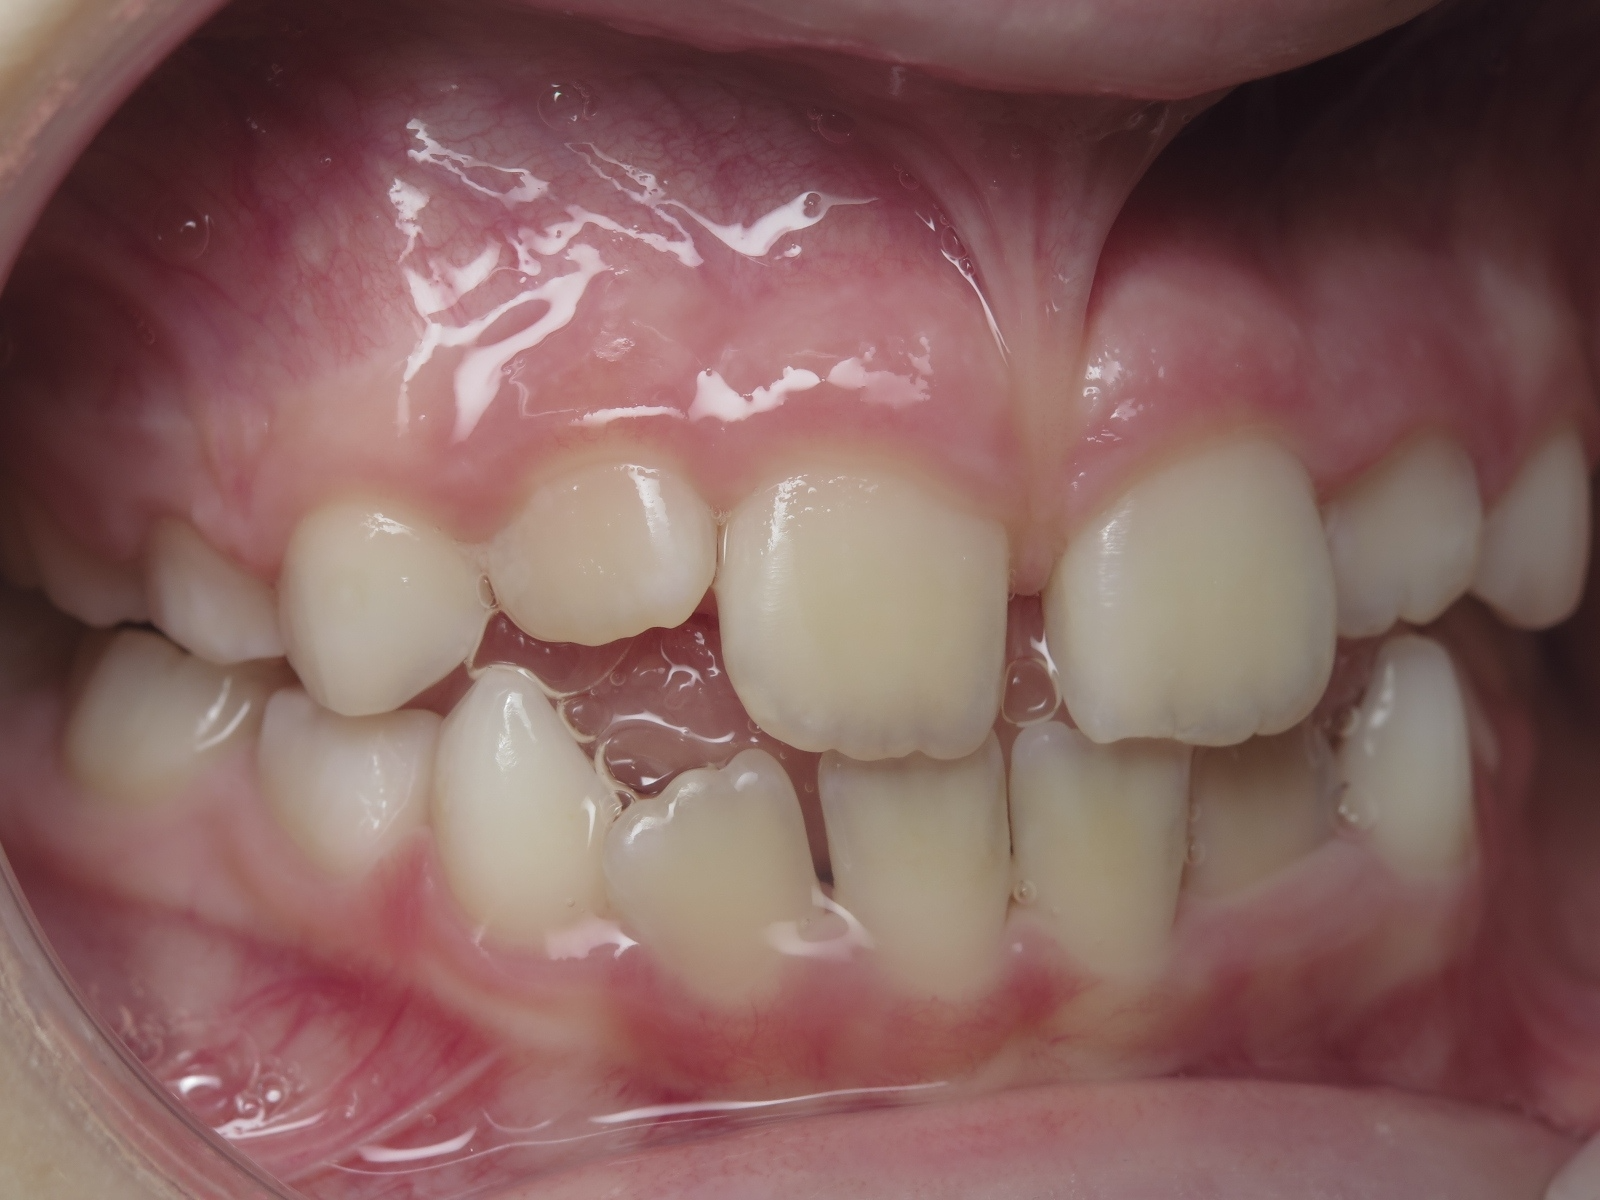

appareillage mobile pendant 3 ans

bilan de début et en cours de traitement